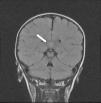

El paciente es hospitalizado y realiza dos convulsiones en racimos durante las primeras 36 h. Como único hallazgo microbiológico, se aísla antígeno de rotavirus positivo en heces. El registro electroencefalográfico fue normal. Por repetición de las crisis, se realiza una resonancia magnética (RM) cerebral, observándose una lesión aislada hiperintensa en T2 y difusión con restricción de la misma bien delimitada de 12×4mm de diámetro, localizada en la porción central del esplenio del cuerpo calloso (figs. 1 y 2). No capta contraste ni produce efecto masa sobre estructuras adyacentes.